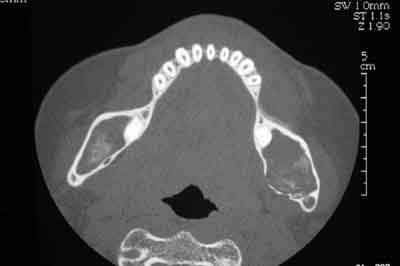

Femme de 40 ans. Aucun antécédent (notamment chirurgical) en dehors d'un DNID, d'un tabagisme modéré (5 paquets-année) et d'une surcharge pondérale. Consulte pour apparition progressive d'une volumineuse voussure dans les 2 vestibles inférieurs et d'une modification consécutive de la forme de la partie inférieure de son visage. A l'examen clinique : tuméfaction dure et fixée dans les 2 vestibules. Sensibilité (V3) normale. Gencive normale. Dents restantes non mobiles, vitales. Pas d'adénopathies palpables. Biologie non faite pour l'instant. Je vous joinds l'OTP et le scan. Diagnostic et options de traitement?

Cas clinique scanner 1 lxblmw - Eugenol

Cas clinique scanner 2 jnd6so - Eugenol

Cas clinique scanner 3 mhlr86 - Eugenol

on voit pas tres bien mais on dirait des phanères, ca te semble possible? Sinon, t as vu la tete de ton os mandibulaire? C'est un artéfact la grosse cavité et les bulles en distal?

du coté de la dent incluse dans le ramus, on peut penser comme diagnostic probable a un kyste d'origine dentaire -image uniloculaire bordée sur son pourtour par une corticale bien individualisée et sur le scanner disparition de l'espace péricoronaire de la couronne avec continuité de toute la cavité.

diagnostic différentiel a faire avec d'autre lésions par ponction et anapat qui confirmeront ou non le diagnostic présomptif.

traitement suivant le diagnoctic de l'autre coté ou

on a le choix entre pas mal de choses dont l'ameloblastome, le kyste multiloculaire, le kyste dentigère, la tumeur de Pindborg

alors?

je ne pense pas a l'ameloblastome, on n'a pas ici l'image caracteristique en "bulles de savon",on n'a pas de projection de petites cavités radioclaires en périphérie et pas de resorption des dents adjacentes qui restent vitales

le kyste multiloculaire montre plusieurs compartiments bien définis , ici l'origine dentaire est possible mais n'explique pas les images multiples derriere la molaire donc peu probable

on peut penser a une tumeur de Pindborg, les pourtours des cavités sont moins nettes et rondes que pour un améloblastome et de plus la tumeur a des bords irréguliers et une tendance à l'envahissement local qui semble confirmé par la disparition de la corticale supérieure sur la partie coronaire de la mandibule

au final l'absence de douleurs et de signes de douleurs des dents par compression ou lesion du V3 laisse espérer le caractère local de la lésion.

Le diagnostic sera forcément établi d'abord par des ponctions et l' histologie qui suivant les resultats dictera le geste chirurgical :

pour des kystes

exerese large en prévoyant les gros risques de fractures

pour des tumeurs types améloblastome ou tumeur de Pindborg , exerese large vu les risques de recidive et reconstruction maxillo faciale

pour des sarcomes , voir equipe cancéro.

Bref, en ce qui concerne ce cas (assez récent), je vous livre le raisonnement qui a été le notre : probables kystes péricoronnaires sur les dents incluses (il n'y a pas de dents "surnuméraires"...). Décision d'abord chirurgical pour énucléation des 3 kystes (les ponctions ne "marchent" pas dans ces lésions) et examens anatomopathologiques extemporanés pour décider, en per-opératoire, de la conduite à tenir (photo 1).

Diagnotic extemporané : kératokystes (!). Les dents incluses se sont donc avérées être un piège diagnostic! Le traitement s'est de ce fait contenté d'un curetage appuyé des paroies osseuses, conservation des 2 nerfs dentaires et, en raison de la taille des kystes mandibulaires et du risque de fracture post-opératoire, nous avons y avons associé une greffe (hydroxyapatite + os autologue (crête illiaque) + PRP) au niveau mandibulaire uniquement (photos 2 et 3)et blocage intremaxillaire pendant 15 jours.

Les suites ont été simples, la reminéralisation des kystes est actuellement en cours (photo 4) et la sensibilité des V3 est normale.